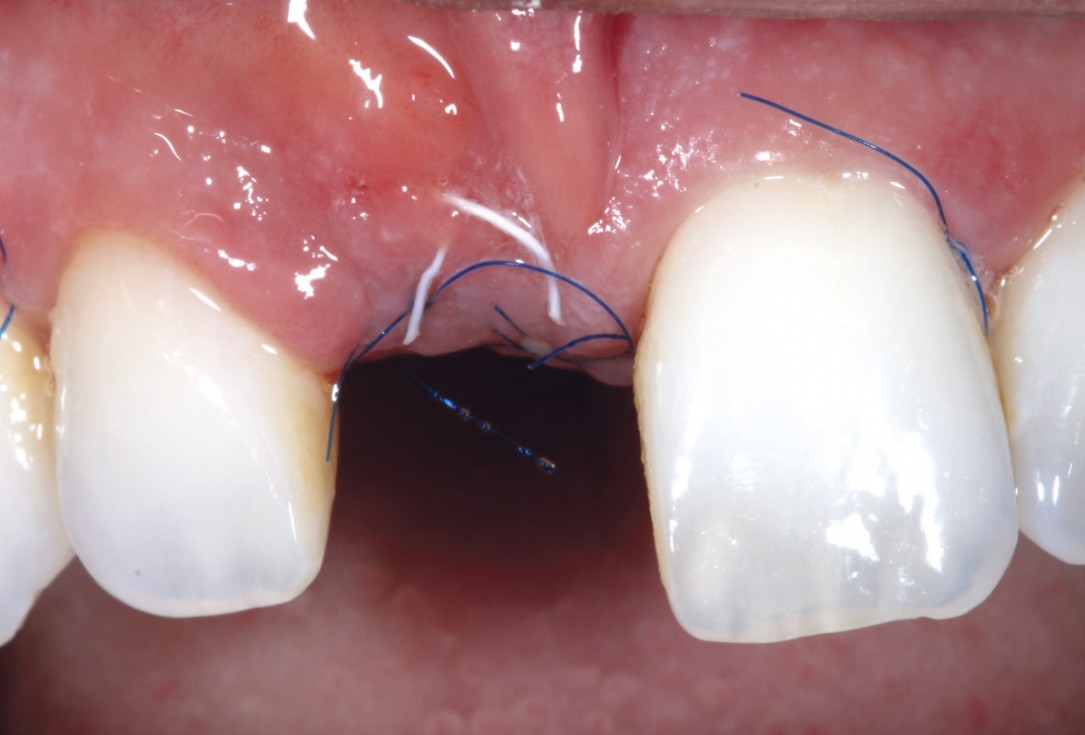

7/11 - Healing after 10 daysmaxgraft® cortico at combined defect palatally and facially - Dr. K. Höckl